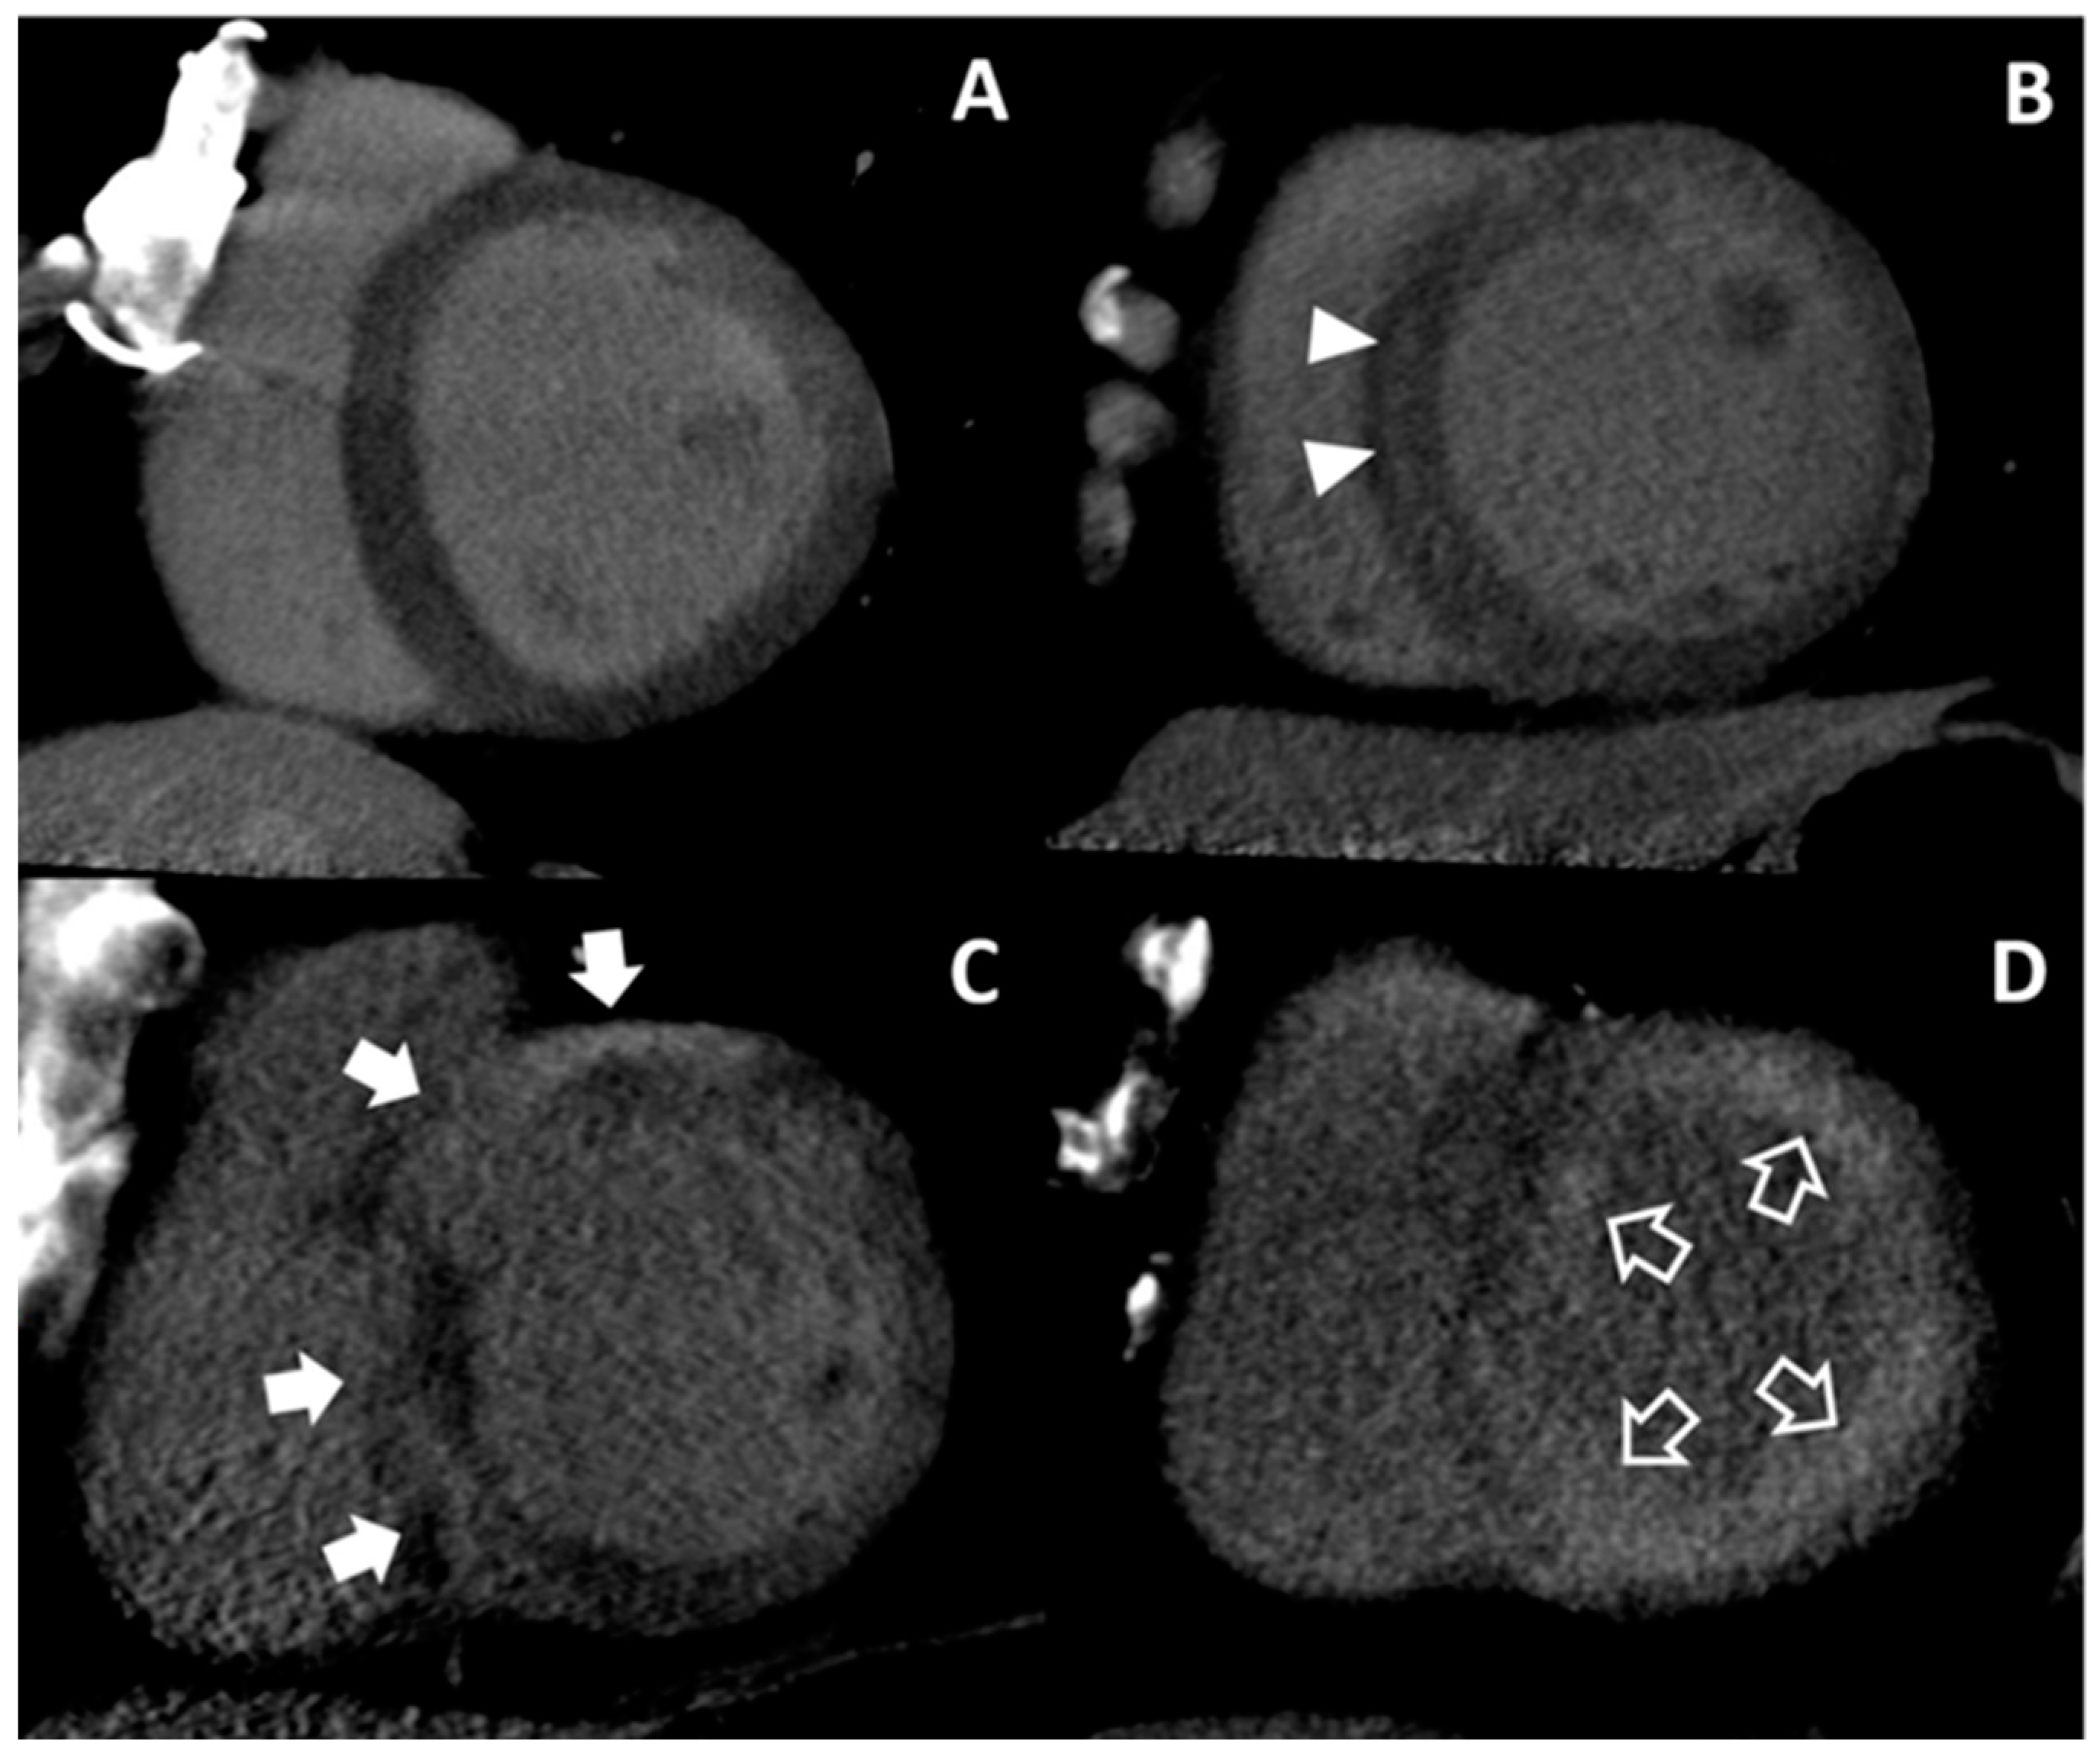

3.4. Tentative Etiologies of HF from Cardiac CT